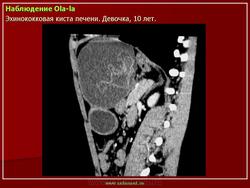

Приводим клиническое наблюдение. Больная Г- ва В.А. 35лет , жалоб не предьявляет. При профилактическом осмотре на УЗИ выявлено: по органам без особенностей, тоны сердца приглушены, пульс 79 ударов в минуту, А/Д 140/95мм.рт.ст. Живот мягкий, безболезненный. Лабораторные данные – общий анализ крови - эозинофилия, общий анализ мочи, коагулограмма в пределах возрастной нормы. При УЗИ органов брюшной полости выявлено два кистозных образования, занимающие правую долю с характерной для Э многослойной капсулой (рис 7а). КТ, МРТ уточнили кистозный характер изменений, их локализацию, наличие толстой капсулы (рис 7б). На основании комплексного анализа поставлен диагноз Э кисты.

Рис 7. Э печени а)УЗИ – кистозное образование с многослойной капсулой, эхогенной взвесью, краевым ослаблением УЗ б, в) РКТ, МРТ – кистозные образования, толстая капсула